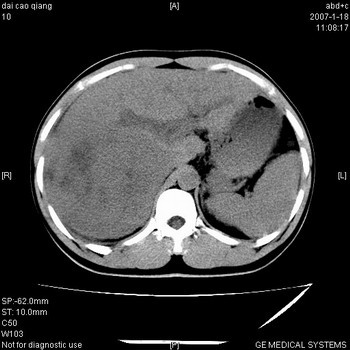

符合巨块型肝癌表现:

1、平扫低密度,增强后表现为快进快出。

2、动脉期可见迂曲的动脉供血血管

3、并可见门静脉右支癌栓形成

4、可见假包膜

5、腹主动脉旁结节影,考虑肿大淋巴结。

肝右叶巨大不均匀低密度肿块,前缘有假包膜,增强明显的呈快进快出表现,门脉右支有癌栓,病人虽然年轻但还是首先考虑肝右叶巨块形肝癌,病人血象高只能说有合并感染。不支持肝脓肿。